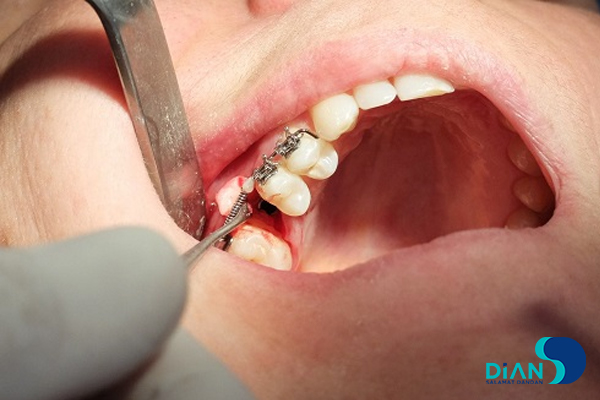

The experienced dentist Dr. Müesser Aktaş from Turkey successfully performed a dental implant procedure using Bio3 Implants in the molar region. For this operation, Dr. Aktaş utilized the Bio3 surgical kit, which is specifically designed to provide precision, ease of use, and efficiency during implant placement. The system’s user-friendly design and reliable components allowed for a smooth and accurate procedure, ensuring optimal results for both the patient and the clinician. This case once again highlights the practicality and advanced engineering of Bio3 Implants, making them a trusted choice for dental professionals worldwide.

Implantation in Molar Area